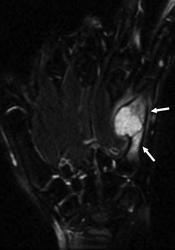

Хондрома периостальная.

Периостальная хондрома (син.: юкстакортикальная хондрома, паростальная хондрома редкая доброкачественная опухоль, состоящая из зрелой хрящевой ткани и расположенная над надкостницей. Обычно она разрушает наружную часть коркового слоя, но не прорастает в костно-мозговой канал. Мужчины болеют в два раза чаще женщин. Типичная локализация - проксимальный конец плечевой и бедренной кости дистальный конец бедренной кости, а также фаланги. В редких случаях одновременно поражается несколько костей. Периостальная хондрома обнаруживается большей частью в метафизарной части, лишь у 30 % больных поражаются диафизы. Опухоль достигает в среднем 2-3 см в диаметре. Она окружена зоной остеосклероза и сопровождается периостальным остеогенезом, так что на границе опухоли с костью образуется грушевидное углубление с четкими контурами. Под микроскопом периостальная хондрома имеет тонкие контуры, она как бы погружена в корковый слой и покрыта надкостницей, как тонкой скорлупой. На разрезе ее ткань синюшно-серая или белая, хрящевые элементы обладают дольчатым строением. Участки обызвествления имеют вид желтовато-белых вкраплений. Эта опухоль состоит из гиалинового хряща, дольки которого разделены фиброзными прослойками или костными балками, местами обызвествленными. Кое-где отмечается проникновение опухолевых клеток в костномозговой канал, на большем же протяжении внутренний контур образован компактной костью.